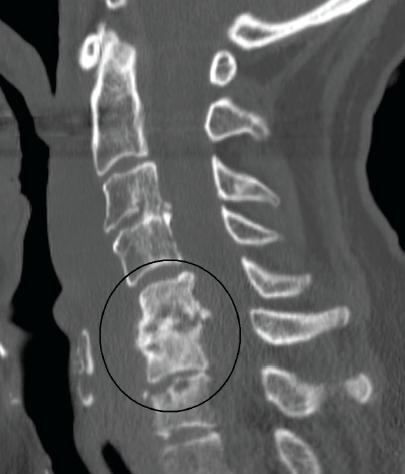

Harsha K. Chandnani, MD; Pirapar Patamasucon, BA

A 20-month-old boy presented with difficulty walking and an abnormal gait secondary to reported back pain. The pain had gradually worsened over the previous 2 months and was relieved temporarily with...